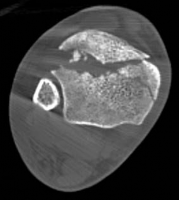

Pre-Operative Planning, Templating, and Patient Positioning

Pre-operative planning is the cornerstone of successful execution in complex pilon-variant tibial shaft fractures. The surgeon must transition from a conceptual understanding of the injury to a concrete, step-by-step surgical blueprint. This begins with high-quality orthogonal radiographs of the entire tibia, ankle, and knee. However, plain films drastically underestimate the degree of articular comminution and central impaction. A fine-cut computed tomography (CT) scan with 2D multiplanar reformats (coronal and sagittal) and 3D surface rendering is absolutely mandatory.

Image

The CT scan allows the surgeon to map the fracture lines, identify the primary articular fragments (Chaput, Volkmann, medial malleolus), and quantify the degree of central die-punch impaction. In an AO/OTA 43C3.3 fracture, where no articular fragment is in continuity with the diaphysis, the surgeon must plan the sequence of reduction. Typically, the fibula is addressed first to restore lateral column length and rotation, provided the fibular fracture is not located at the level of the syndesmosis where fixation might interfere with the lateral surgical approach to the tibia.